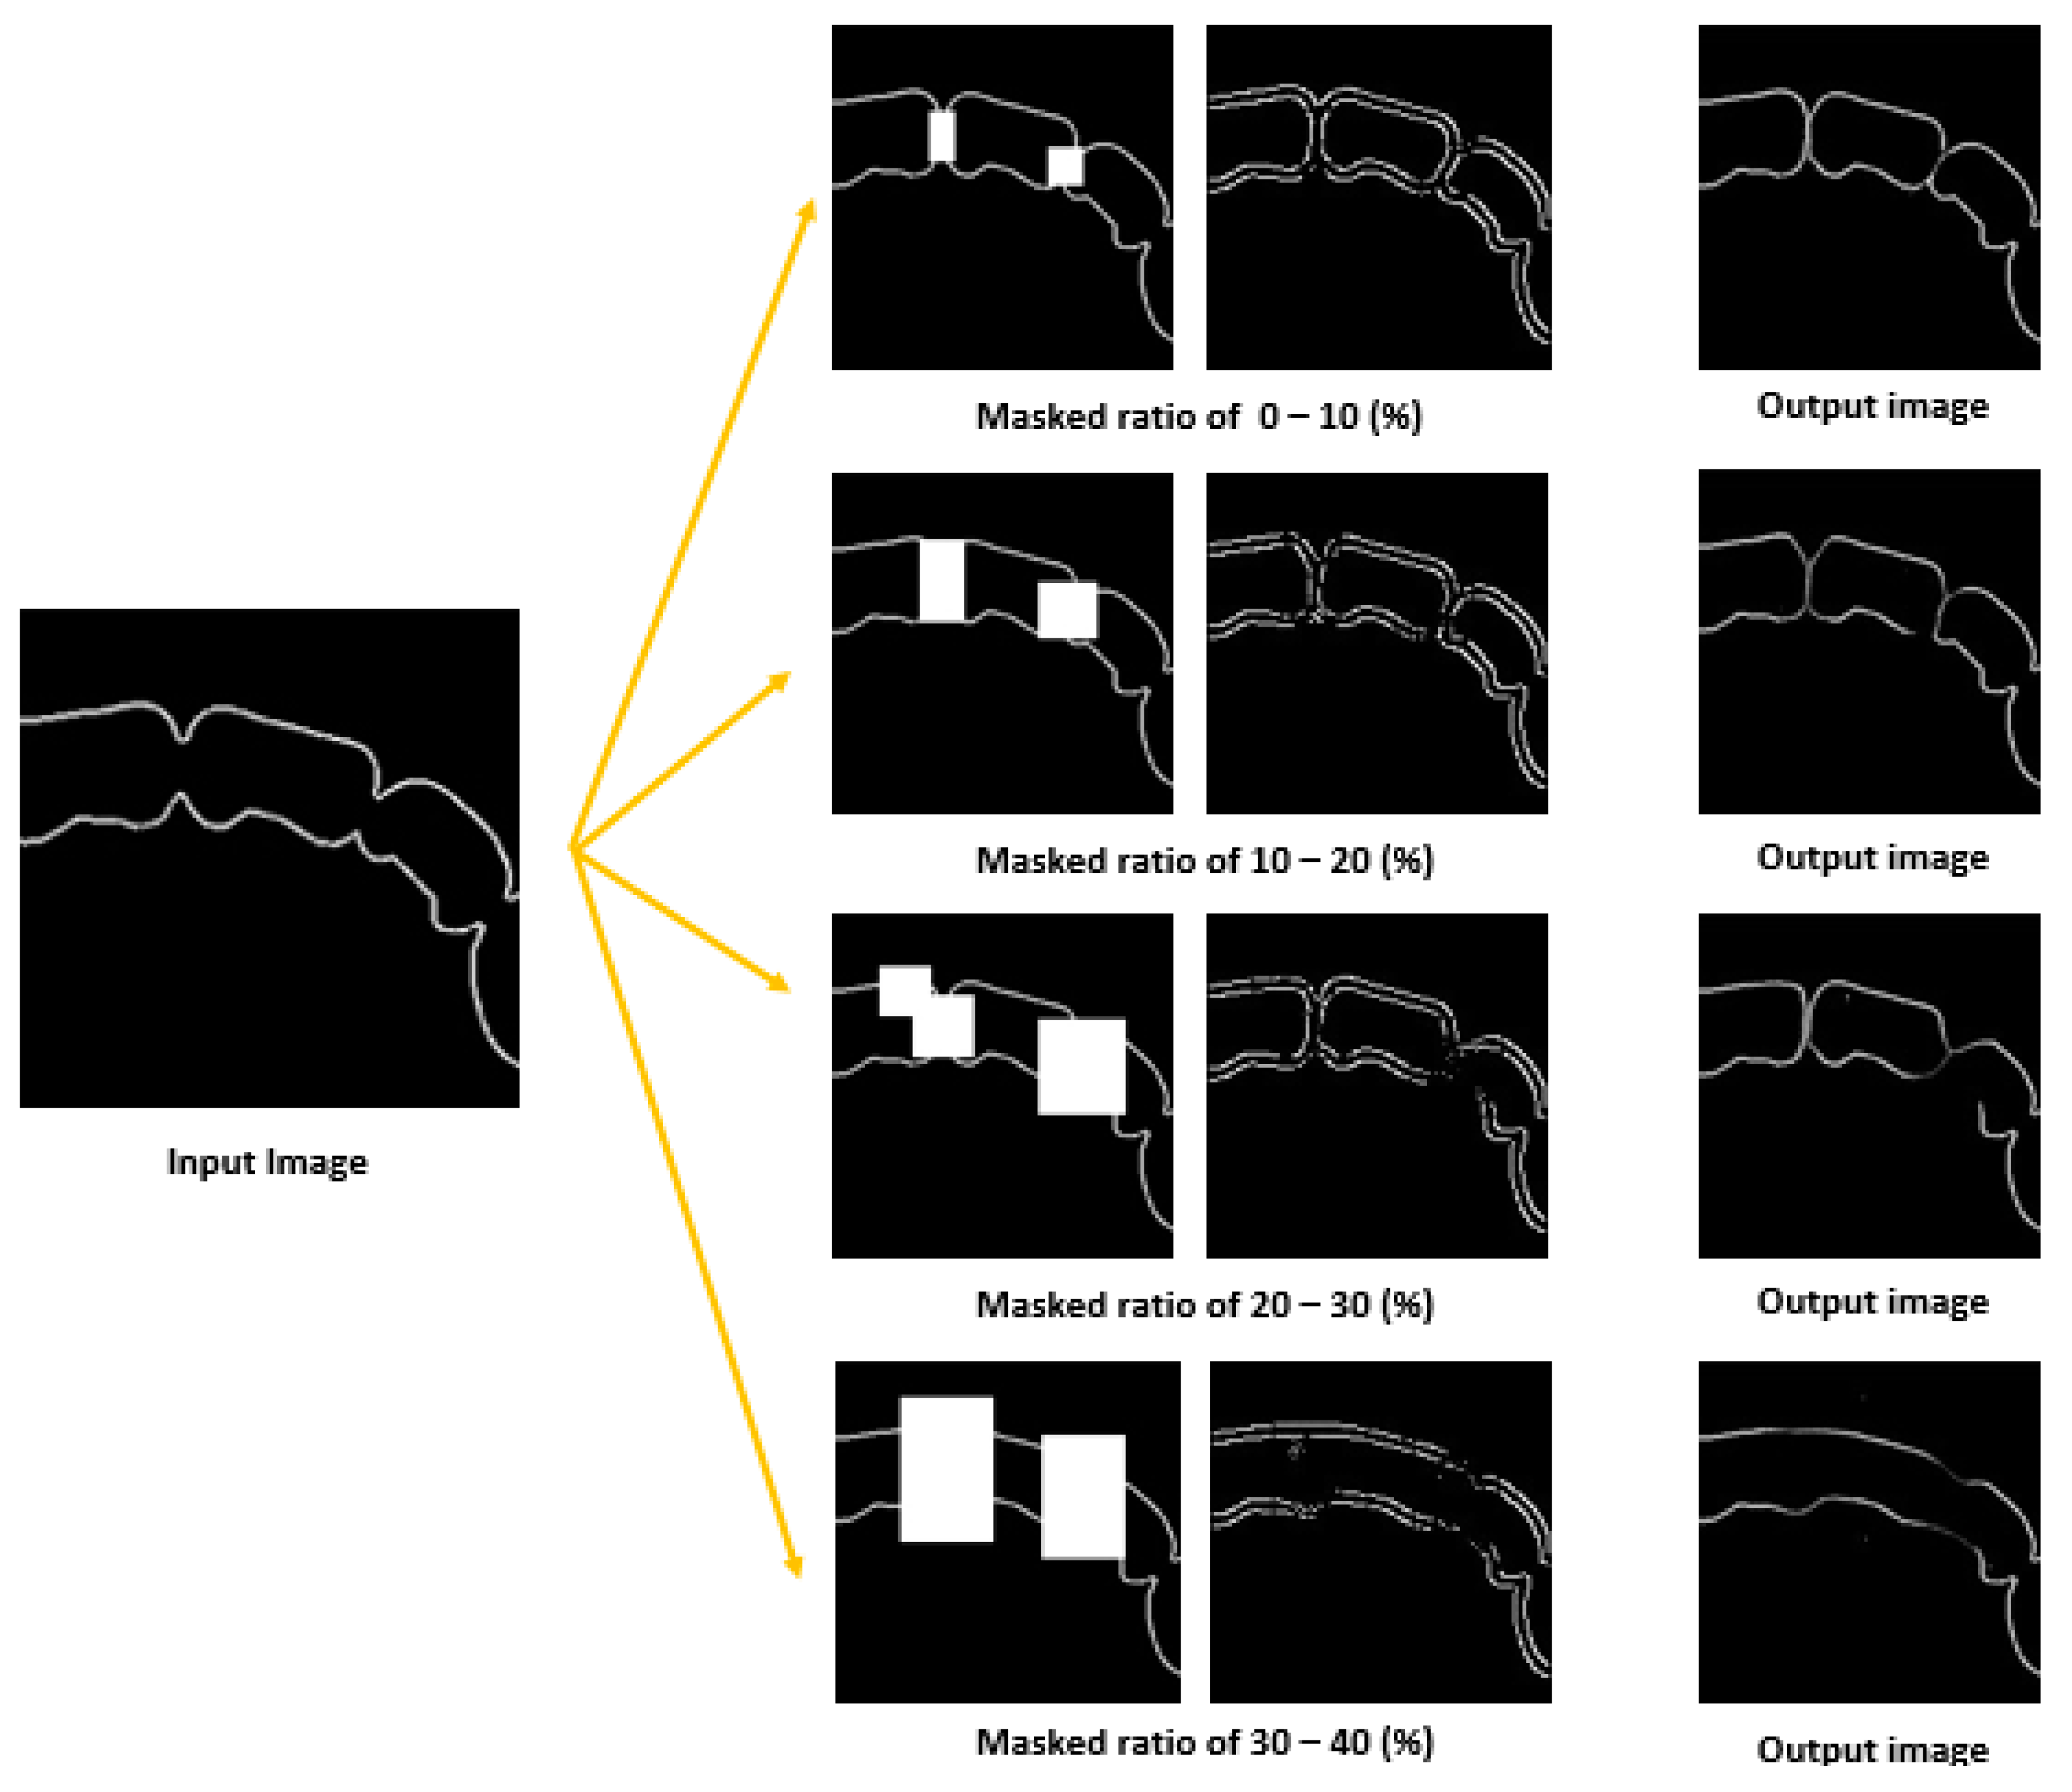

2.3.1. Data Preparation

2.3.2. Training Steps

3.1. Result of Image Completion